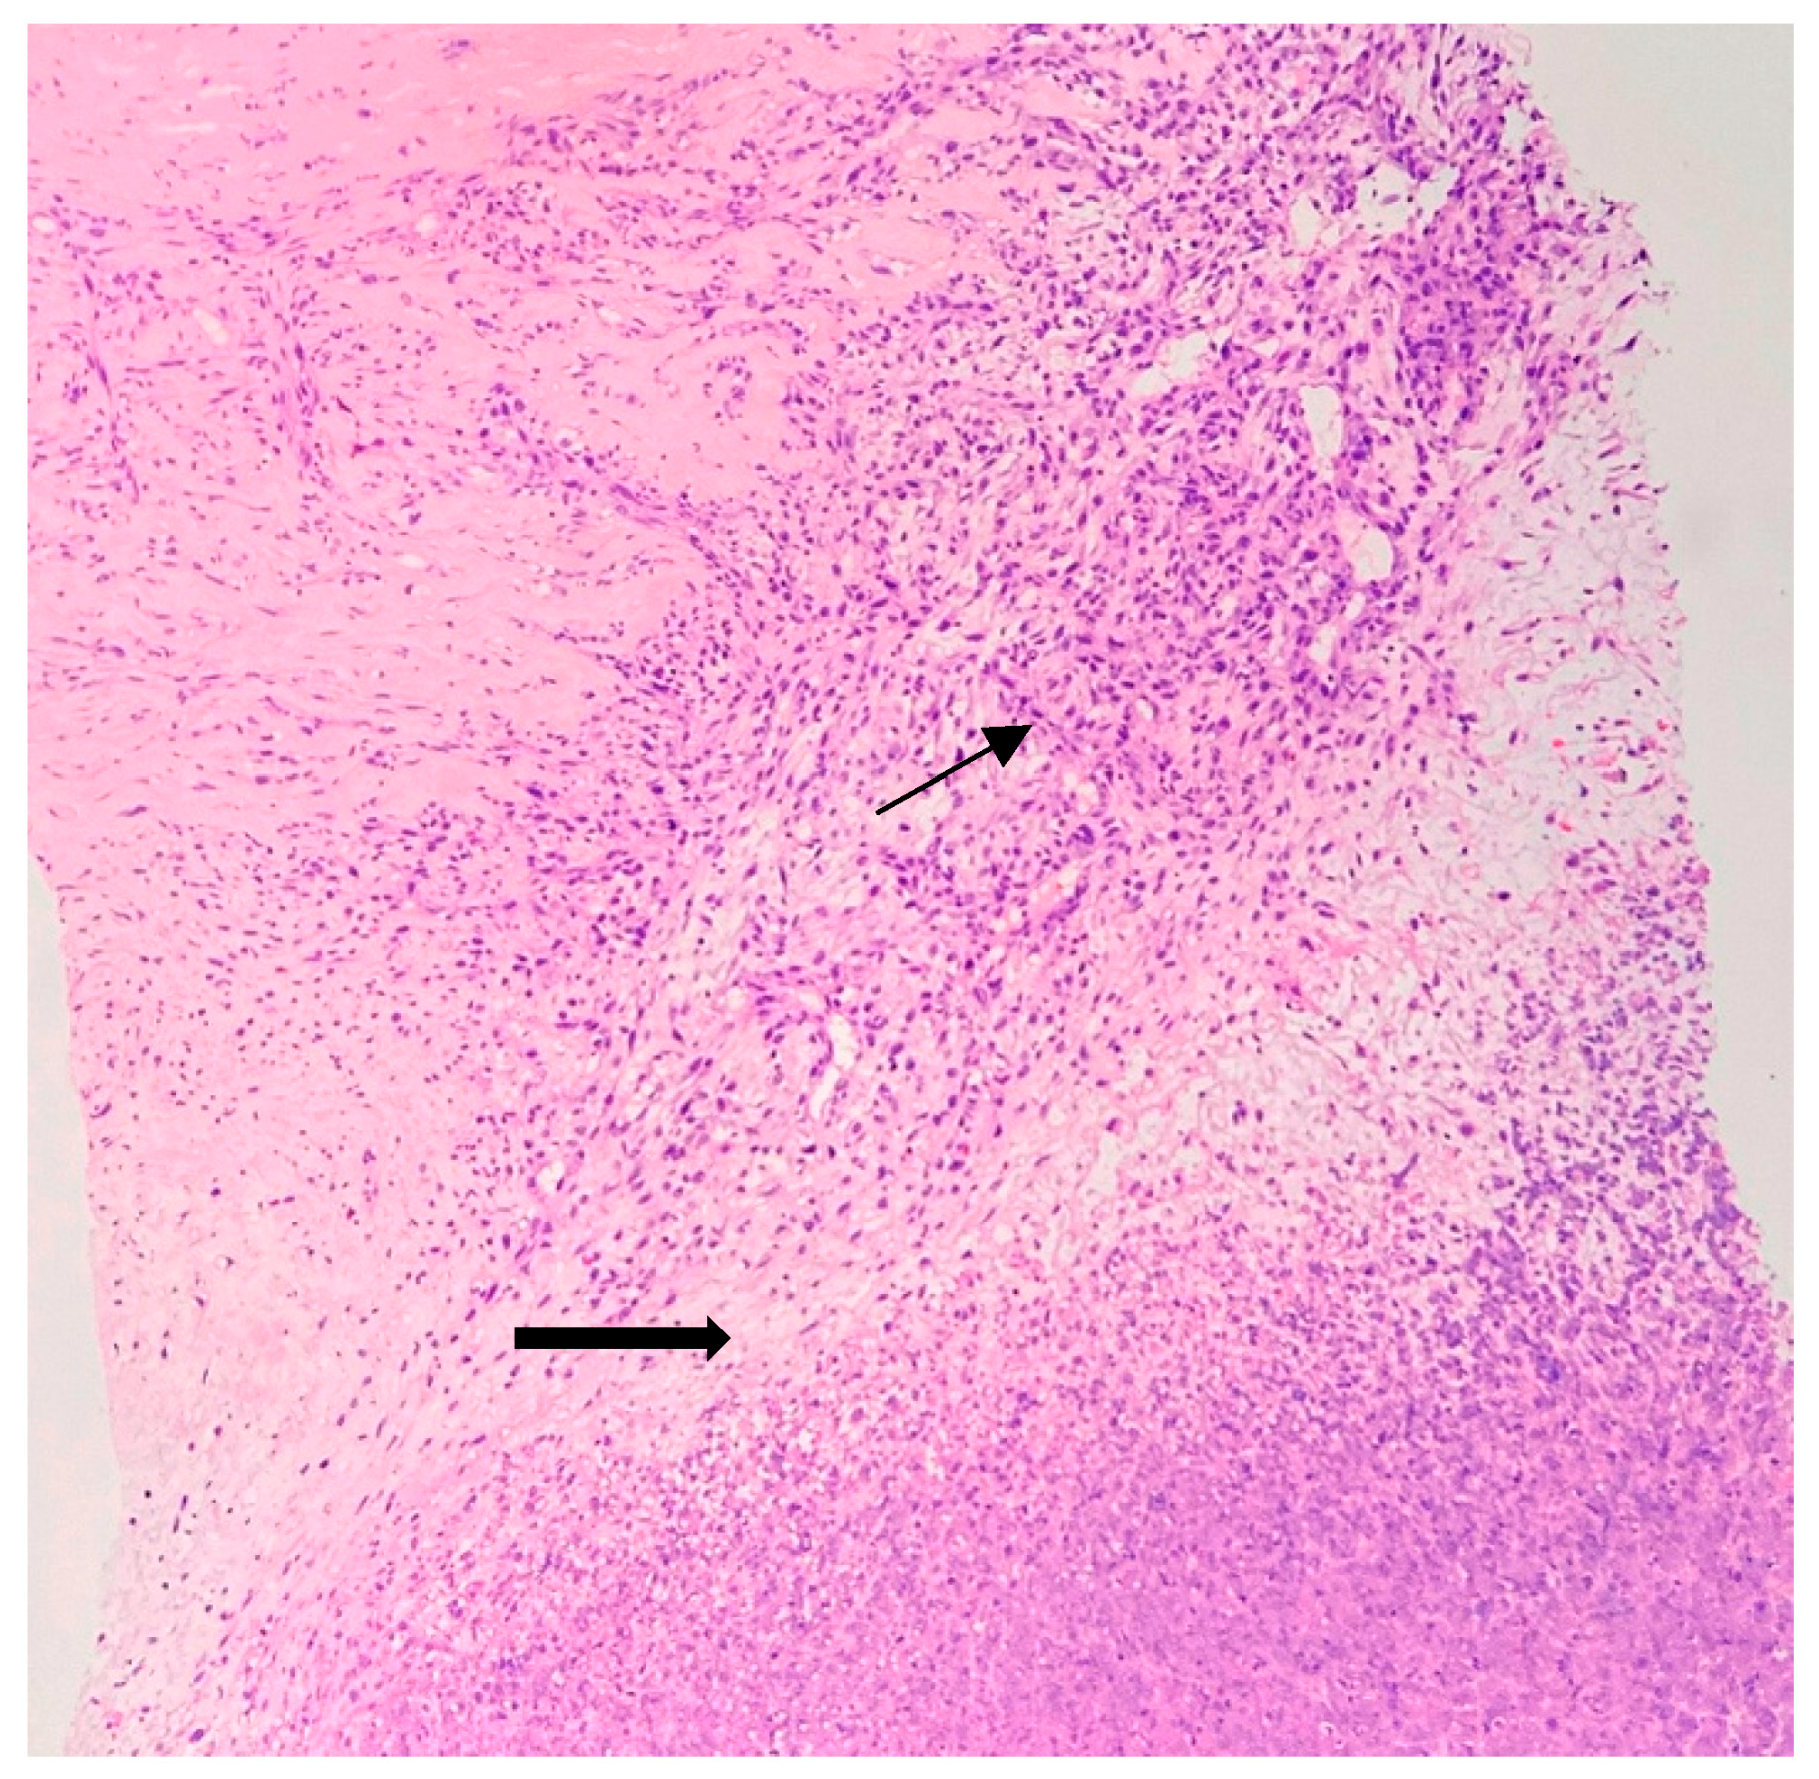

2. Case Report